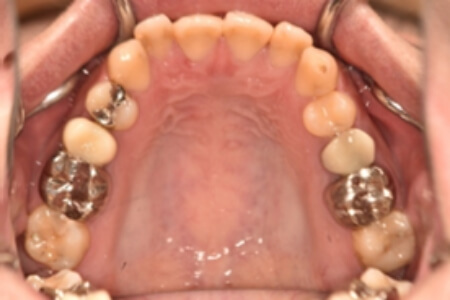

| 治療内容の詳細 | 初診時26歳の男性で、受け口を気にされ来院されました。 検査の結果、下顎前突、上顎前歯部叢生および上顎側切歯反対咬合を伴うアングルⅢ級不正咬合と診断しました。 先ず、前期治療として、リンガルアーチを使用し、上顎中切歯を前方へ移動させ、反対咬合の改善を行いました。 その後、マウスピース型矯正装置(インビザライン)で配列を行いました。 治療期間としては1年8か月でした。 |